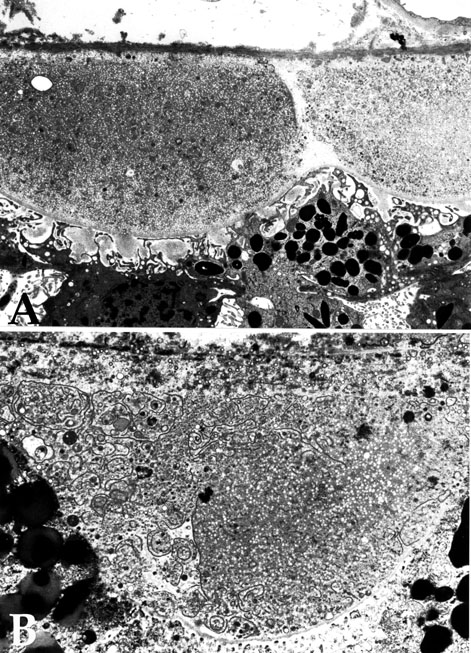

Figure 3. Electron micrographs of second drusen phenotype with lucent, vesicular material

Transmission electron micrograph depicting a second drusen phenotype, which is largely homogeneous but possesses small, uniform electron lucent spherical elements. Higher magnification images are depicted in Figure 2B and Figure 4. Curvilinear profiles may also be observed in this phenotype (B and Figure 4)